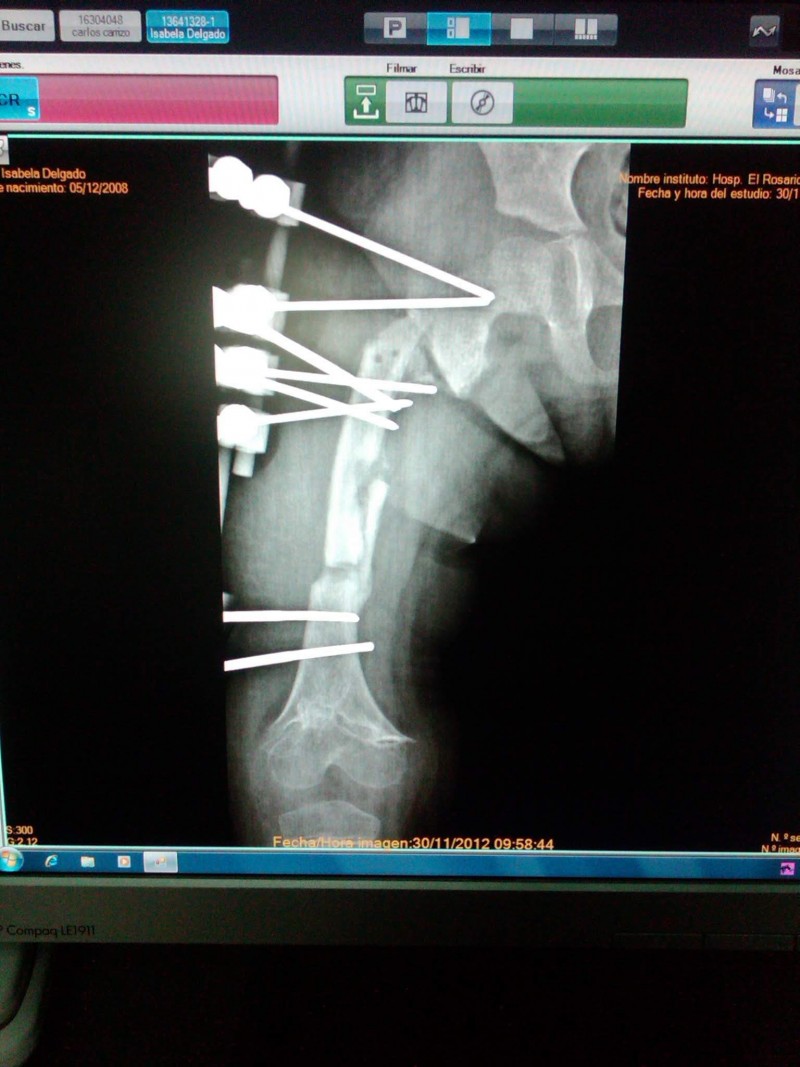

Tengo 44 años y trabajo como secretaria en un hospital, gano como unos 3$ mensuales y tengo 2 hijos un varón y una hembra. Mi hija tiene un condición desde recién nacida a causa de una mala praxis mientras le colocaban una inyección lo que produjo una Osteomielitis en su pierna derecha desde su cadera hasta la rodilla causando varios problemas entre los cuales está el deterioro de los nucleos de crecimiento distales y proximales y por lo que el fémur no crece como debería teniendo que ser sometida (durante todo su crecimiento) a cirugias para corregir algunos de las deformaciones causadas por la infección y para hacer crecer el fémur de manera mecánica, mediante un tutor externo de alargamiento. Dichas cirugias tienen un costo de unos 4.500 - 5.000$ que no tengo la manera de obtenerlos además de que soy madre soltera. Nosotros vivimos en una zona rural en casa pequeña que se está desmoronando a mi hija ya le cuesta cada más caminar y caminamos mucho, ya que su marcha compromete mucho su rodilla, cadera y columna porq la diferencia entre una pierna y otra ya es de unos 15 a 18cm. Ya es urgente que sea operada